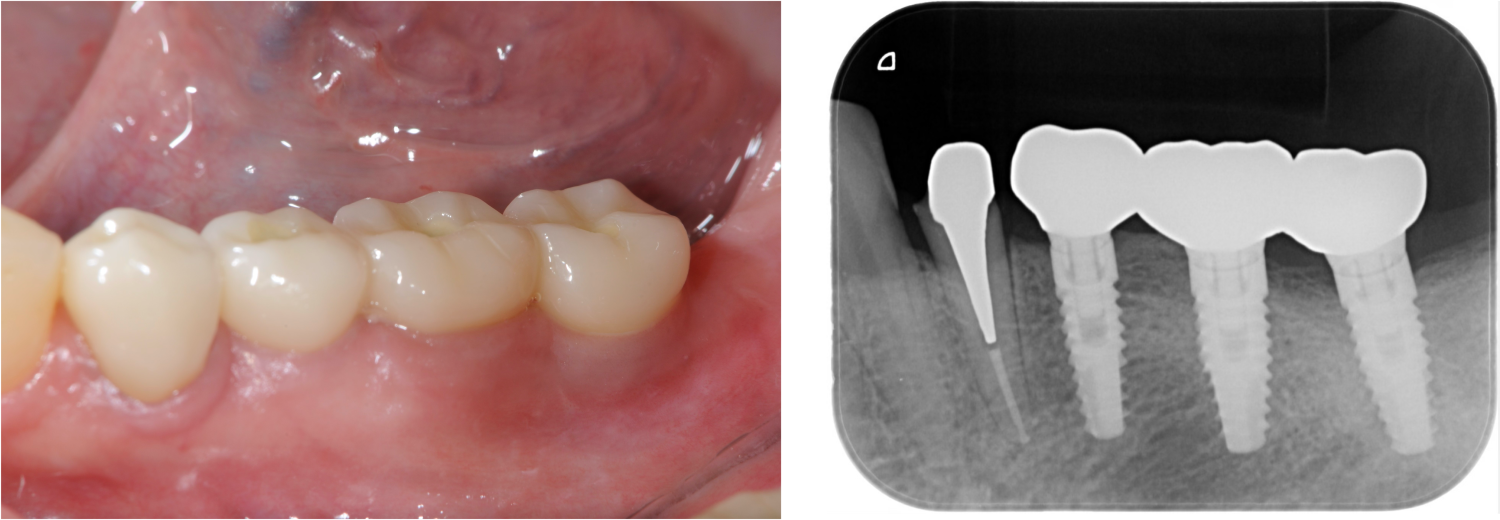

下顎臼歯部が欠損した患者さんのインプラント治療の症例②(うえだ歯科)

上田大介(うえだ歯科)

症例詳細

| 主訴 | 全顎治療希望、下の奥の歯が無いので全く噛めない。綺麗で噛めるようになりたい |

| 治療内容 | 下顎臼歯部欠損放置のため、臼歯部においてスペースがないため、全顎治療を行い咬合再構成を行う。 早期においてインプラント治療、咬合関係を模索した後、全顎にわたりセラミックによる補綴治療、その後メインテナンスに移行 |

| 治療費 | 5,410,000円(税込)(インプラントすべて含む) |

| 治療期間 | 1年8ヶ月 |

| 治療回数 | 80回 |

| 想定されたリスク | 食いしばり(パラファンクション)によるセラミックの破折、歯の破折 |